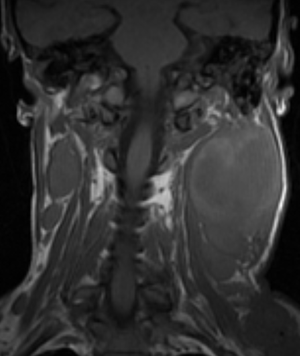

МР-диагностика новообразований мягких тканей шеи

- Оценка регионарных лимфатических узлов